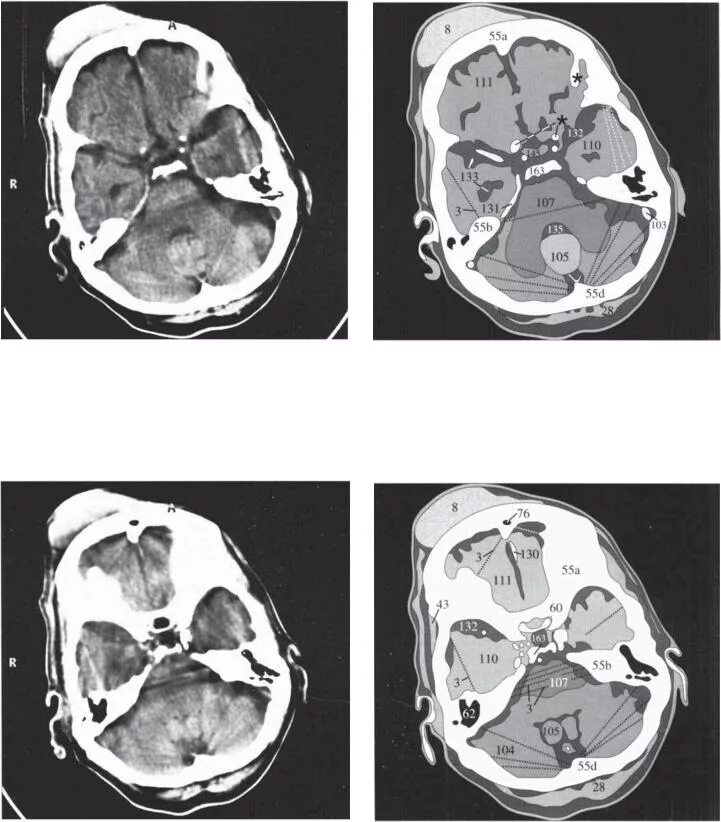

Кт тканей